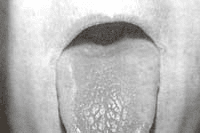

Además, con presencia de lengua seca despulida ( Figura 2) y sígnos activos de conjuntivitis y resequedad.

Lengua seca despulidaFigura 2